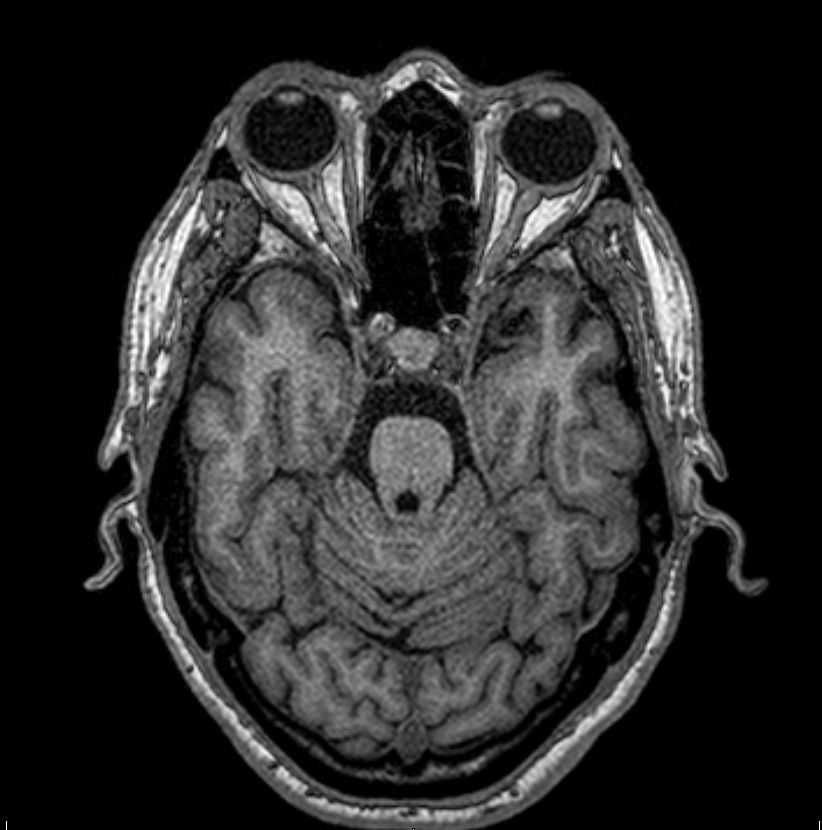

Results: A 65 year old male patient with just a past history of smoking who presented to the neurology consult with a 5 year history of slow progressive gait instability, dizziness. sexual dysfunction and urinary incontinence. His neurological examination revealed an ataxic gait, with right rigidity and bilateral dysmetria and bradykinesia. Laboratory work up revealed negative infectious and rheumatologic tests, a hyperproteinorrachia with no pleocytosis in CSF, a normal Dat Scan, and a brain MRI with severe pons, middle cerebellar peduncles and cerebellar atrophy (figure 1 and 2). Paraneoplastic panel was positive in two different samples for Yo-1 antibodies. Screening for underlining neoplasia was negative for breast, lung, gastric and prostate cancer. The patient received a 5 days cycle of IV immunoglobulin with a marked improvement in his gait, balance and limb symptoms.

Figure 1. Pons atrophy